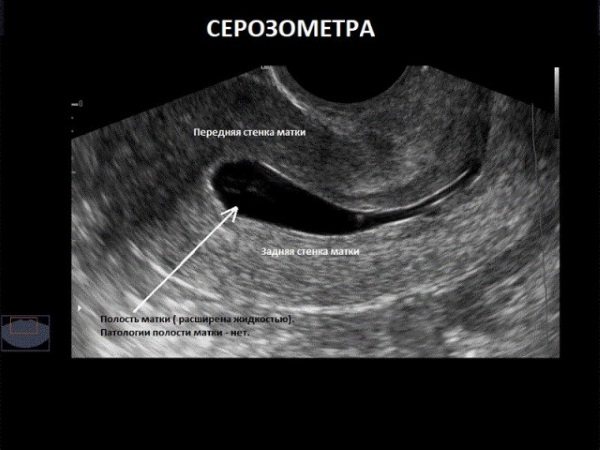

Чаще всего гинеколог может поставить диагноз серозометра уже на первичном осмотре в зеркалах. Признаками служат увеличение размеров матки, присутствие серозных выделений на стенках вагинального тракта. После женщине обязательно рекомендуется прохождение УЗИ – трансабдоминального и трансвагинального.

Это простое исследование покажет не только наличие серозометры, но и поможет установить ее причины:

- врожденные пороки развития матки (обычно у молодых девушек);

- опухоли;

- спайки у женщин в климаксе, постменопаузе;

- гиперплазию эндометрия и эндометриоз и т.д.